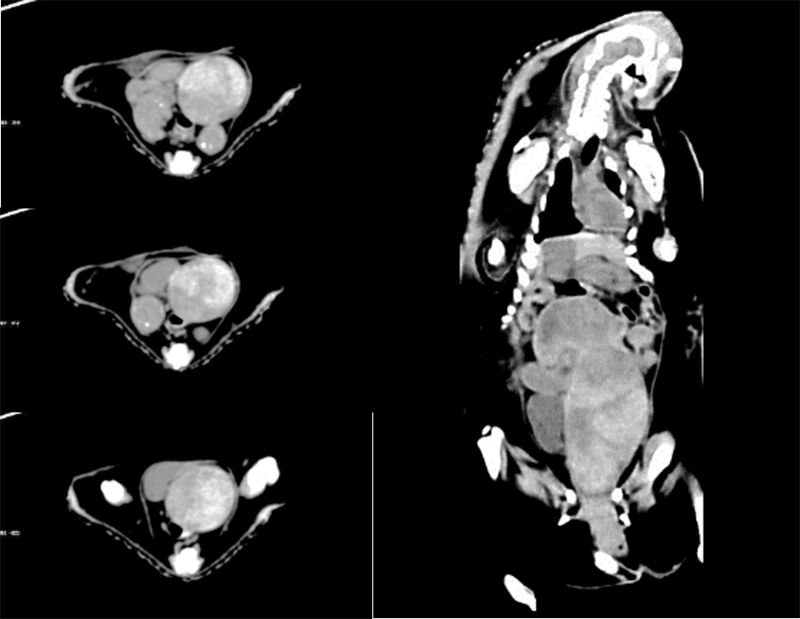

臨床畫廊